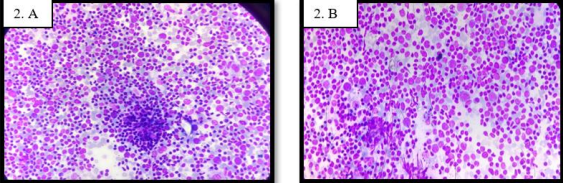

Cytological analysis of reactive lymph node reveals lymphoid cells with variable maturation intermixed with immunoblasts, and tingible body macrophages (Figure 2.A & 2.B).

In our study, we observed that the categorization of the cause of lymphadenopathy into necrotizing granulomatous lymphadenitis, granulomatous lymphadenitis, Suppurative lesions and reactive lymphadenopathy could be reliably done by FNAC, (Figure 1& 2). A high sensitivity (71.4%) and specificity (91.5%) of FNAC was reported in previous studies for the evaluation of lymphadenopathy [5]. For patients with a known history of tuberculosis and tuberculosis contact in whom a subsequent enlargement of lymph node occurs, a cytological diagnosis of tuberculosis helps in avoiding unwanted surgical biopsy for confirming tuberculosis.